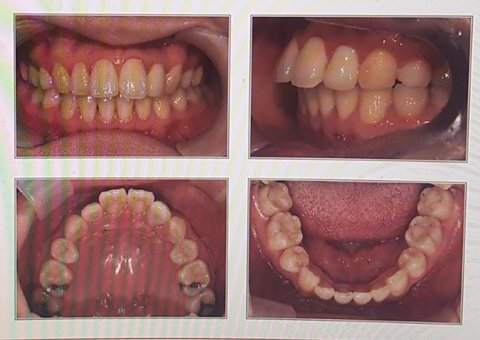

아래 사진은 제가 2018년 재교정을 하기 전 찍은 사진입니다.

앞에서 볼 때 윗니 아랫니 수평 수직배열이 무난히 맞으나

옆에서 보면 윗니는 튀어나오고 아랫니는 안쪽으로 누워 있어서

누운 치아를 펴고 윗니는 넣고 아랫니 전체를 앞으로 끌어내는 진료를 시작했습니다.